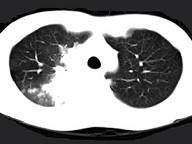

问题 男,28岁,咳嗽,咯血,消瘦盗汗1个月余,影像学检查如图。最可能的诊断为 ( )

选项 A.类风湿肺炎 B.右上肺周围型肺癌 C.右上肺浸润型肺结核 D.右上肺炎性假瘤 E.右上肺曲真菌感染

答案 C